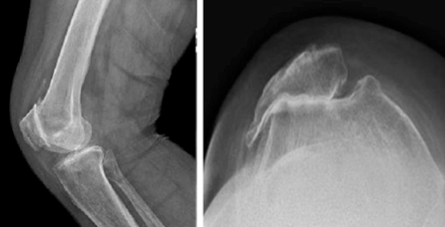

- Ακτινογραφίες:

- Προσθιοπίσθια λήψη: βοηθά στην επιβεβαίωση ότι το έσω και έξω διαμέρισμα του γόνατος δεν πάσχουν από σημαντική αρθρίτιδα

- Πλάγια λήψη: Αξιολόγηση του βαθμού φθοράς του επιγονατιδομηριαίου διαμερίσματος

- Λήψη καθ’ εφαπτομένη: βοηθά στην απεικόνιση του βαθμού φθοράς μεταξύ της επιγονατίδας και του μηριαίου